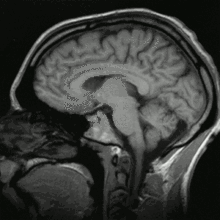

Image IRM d'une tête humaine en pondération T1, en coupe sagittale. La tête est vue de profil, regardant vers la gauche. On y voit le cerveau en gris clair entouré de liquide cérébrospinal (en noir), la boîte crânienne et le cuir chevelu ; sur d'autres coupes, on peut voir les globes oculaires et, au niveau du plan médian, différentes structures du névraxe (face interne d'un hémisphère cérébral, corps calleux, cervelet) ainsi que d'autres parties de l'anatomie (langue, fosses nasales, etc.).